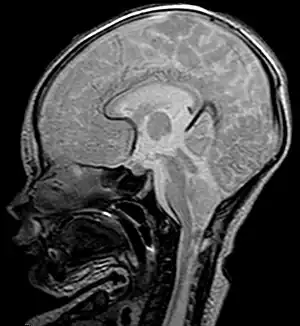

Este tipo, también denominado malformación de Chiari clásica o malformación de Arnold-Chiari propiamente dicha, involucra la protrusión de estructuras cerebelosas y también del tallo cerebral a través del foramen. A menudo el vermis está, además, incompleto o ausente, y todo el cuadro suele acompañarse de hidrocefalia y mielomeningocele a nivel lumbar. Esta complicación puede derivar en parálisis parcial o total por debajo del mielomeningocele.[8]

Tipo 2

Tipo 3

La forma más grave de la anormalidad. El cerebelo y el tallo cerebral, herniados, se introducen en el canal medular cervical, a menudo acompañados del cuarto ventrículo cerebral y comprimen la médula espinal. En algunos casos raros, el tejido cerebeloso herniado asoma por una abertura anormal del hueso occipital, formando una bolsa llamada encefalocele occipital, que puede contener incluso tejido cerebral. Este tipo de Chiari produce serios síntomas neurológicos.